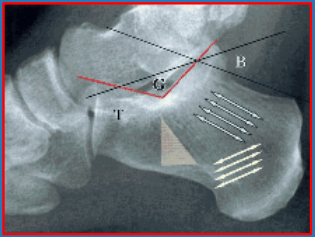

11 后足—Haglund's deformity

后跟骨角/Fowler和Philip角(Fowlerand Philip angle,FPA):指跟骨外后上斜面与跟骨下表面切线之间的夹角,正常值范围为44~69°,≥75,65?为异常。

后跟全角(posterior heel total angle,PHTA):跟骨外后上斜面与水平线的夹角:正常值范围为64~89°,≥89°为异常,考虑了α角(pitch angle),即足弓异常。